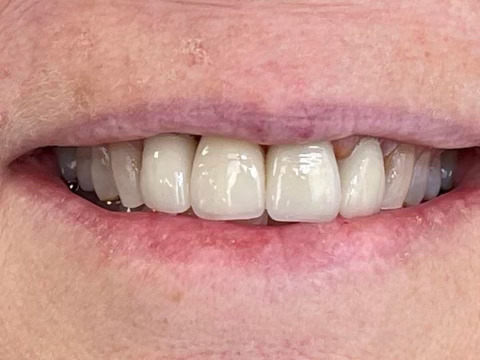

Case Study: Dental Implant

A patient with a missing tooth received a dental implant, restoring both function and aesthetics.